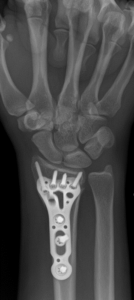

Acute fracture care of the pelvis and the extremities